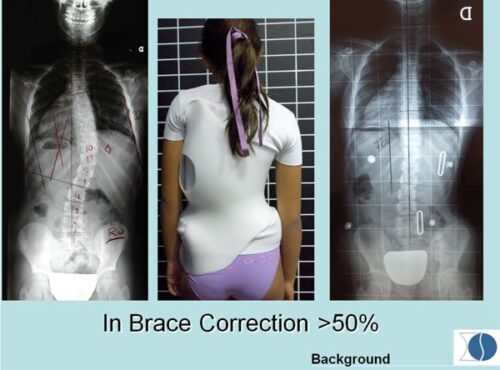

يُعد الحزام الطبي أحد أكثر الطرق فعالية لعلاج اعوجاج العمود الفقري عند المراهقين ومنع تفاقم الانحناء خلال مرحلة النمو. ومع اقتراب انتهاء فترة العلاج، يتساءل الكثير من الأهل: ماذا يحدث بعد إزالة الحزام؟ هل سيعود الانحناء؟ وكيف يمكن متابعة الحالة والحفاظ على النتائج؟ هذا المقال يقدّم إجابات مفصلة بطريقة سهلة الفهم للأهل، مع التركيز على الوقاية والمتابعة بعد التوقف عن الحزام.

نجاح الحزام الطبي لعلاج اعوجاج العمود الفقري عند المراهقين لا يعتمد على ارتدائه فقط، بل على تفاصيل دقيقة مثل تصحيح دوران الفقرات الأولى وسرعة هذا التصحيح. متابعة الأهل مع الطبيب، الالتزام بعدد ساعات الارتداء، واستخدام الحزام المصمم خصيصًا لكل طفل، جميعها عوامل تزيد من فعالية العلاج وتمنح الطفل فرصة أفضل لنمو ظهر مستقيم وحياة طبيعية.

التطور الكبير في تصميم الأحزمة الطبية جعل علاج اعوجاج العمود الفقري عند المراهقين أكثر نجاحًا وأقل إزعاجًا. باستخدام تقنيات التصوير الثلاثي الأبعاد والمحاكاة الرقمية، أصبح الحزام أكثر خفة وراحة، ويعطي نتائج أفضل في تصحيح الانحناء والتواء العمود الفقري.

امنح طفلك فرصة أفضل لمستقبل صحي مع حزام PioBrace المتطور من مركز الرواد. يتميز هذا الحزام بتقنيات تقويم متقدمة تضمن نسبة تصحيح عالية لاعوجاج العمود الفقري، مع اعتماد فريق طبي متخصص يراقب التقدم بشكل مستمر لضمان عدم تفاقم الانحناء مستقبلاً. اختروا مركز الرواد، حيث تلتقي الخبرة الطبية بأحدث الابتكارات، لنوفر لطفلكم علاجًا مخصصًا وآمنًا يعيد التوازن لجسمه بثقة واحترافية. صحتهم أمانة ونحن هنا لنحافظ عليها.

لماذا يجب عليكم اختيار حزام PioBrace؟

- راحة استثنائية: يتميز حزام PioBrace بتصميمه الذي يوفر أقصى درجات الراحة للأطفال طوال فترة العلاج.

- فعالية مثبتة علميًا: يساعد الحزام في إيقاف تقدم الاعوجاج وتقليل الحاجة إلى التدخل الجراحي.